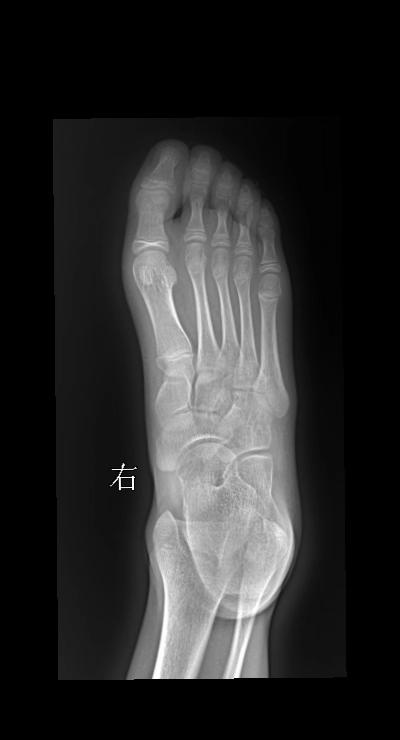

足外伤 14岁 女 第一跖骨软组织肿胀

2025-09-19 19:19